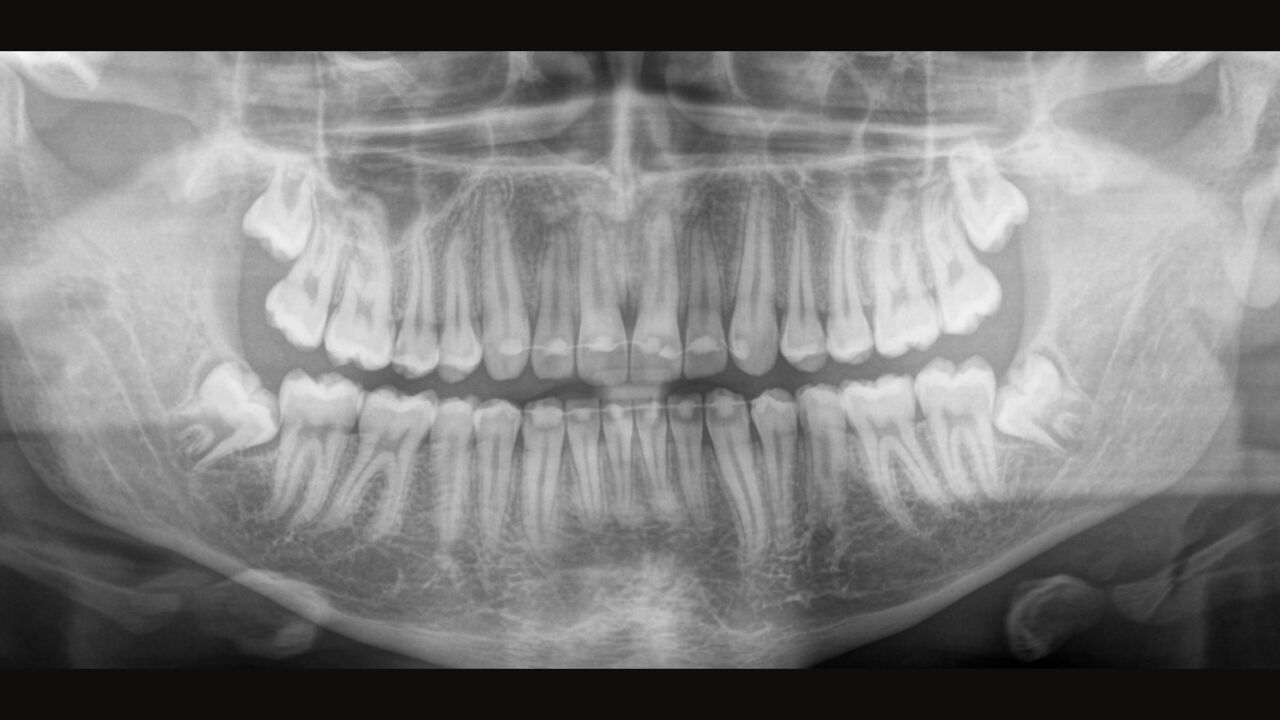

El sensor de conversión directa (Direct Conversion Sensor, DCS) ha revolucionado el estándar de la imagen panorámica. Las imágenes radiológicas se convierten directamente en señales eléctricas. Por lo tanto, no hay pérdida de señal debido a conversión de la luz, como es el caso de los sistemas convencionales. El resultado: imágenes con un alto nivel de nitidez y contraste, incluso con una dosis de radiación extremadamente baja. Para obtener información de diagnóstico precisa a fin de apoyar el tratamiento objetivo.

La imagen a continuación muestra una radiografía panorámica con y sin tecnología DCS. Usando la flecha, arrastre el control a través de la imagen para ver la diferencia que el sensor de conversión directa hace con la calidad de la imagen y las posibilidades de diagnóstico.